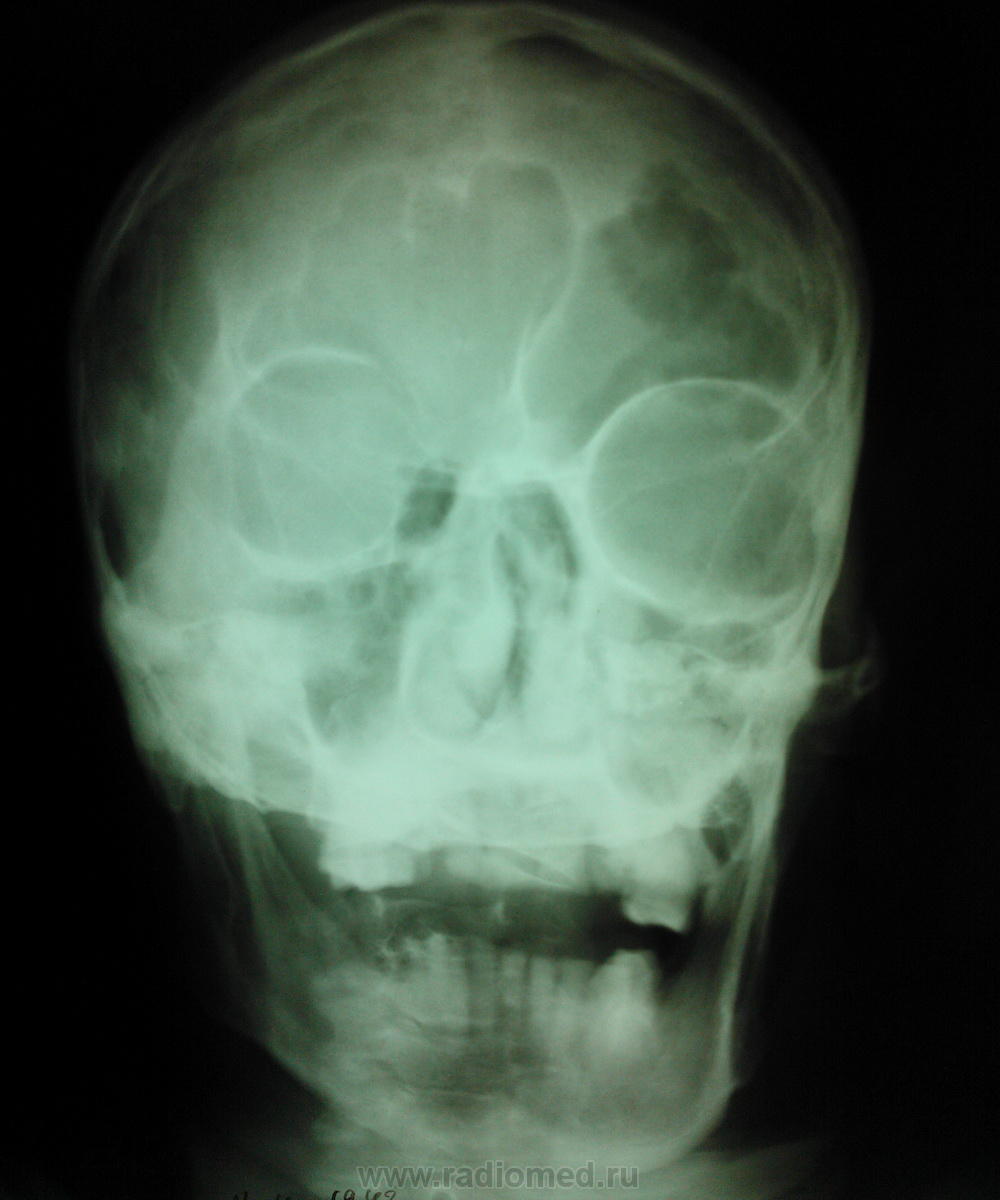

мужчиа 42 года рождения. находится в реанимации с диагнозом ОНМК с правосторонним гемипарезом, повторон. в анамнезе комбинированный митральный порок сердца. Что это такое в височно теменной области слева, энхондрома?  метастаз? на рентгеннограмме ОГК расширен правый корень (центральный рак?) и круглая тень в левом легочном поле (метастаз?). какие будут предположения? в анализах ничего особенного ни СОЭ повышенного ни лейкоцитоза. можно было бы ЛТГ сделать но рентгенаппарат сломался (сгорели инверторы) - так что томки врят ли ожидаются в близжайшее время.

На снимках черепа ничего патологического, особенности строения костей черепа. В легких( на снимке четко видно слово "лЁжа") м. предположить пневмонические, застойные дела, порок сердца, ревматические - или возрастные проблемы. Затемнение в в/д справа - возможна и "инфаркт- пневмония". Корень расширен- скорее, не к онкологии, а к сердечным проблемам.

То что в костях черепа более вероятно метастазы, менее верятно множественная миелома.. Правый корень расширен, но возможно из-за того что снимали лежа + с/с патология, не похоже что там опухоль

Грудная клетка кардиального больного (скорее всего с поражением клапанов) и  застоем в малом круге/артериальной гипертензией.

В черепе тоже не метастазы.

Почему не метастазы?. Они с относительно четким контуром бывают. Тут в теменной кости участок, и похоже что не один, в лобной кости, затылочная тоже вопросы вызывает.. Не знаю как стрелку нарисовать, но в одном участке если присмотреться тонкие спикулы - периостальная реакция..

1. И все равно придумываете. 2. Эта картина похожа на гемангиому (что и показал Валентин Львович). 3 Как бы вам объяснить? Короче, была бы шишка при метастазе таких размеров.

Все поняла, глупость написала - смутил рваный вид костей черепа, а это просто видимо из-за укладки шов так получился

Гемангиома. Типичная локализация в области теменного бугра, гладкий, четкий контур, фестончастые края, намечающаяся звездчатая структура. Все типично. Хрящевых опухолей в костях свода не бывает. Там нет хряща.